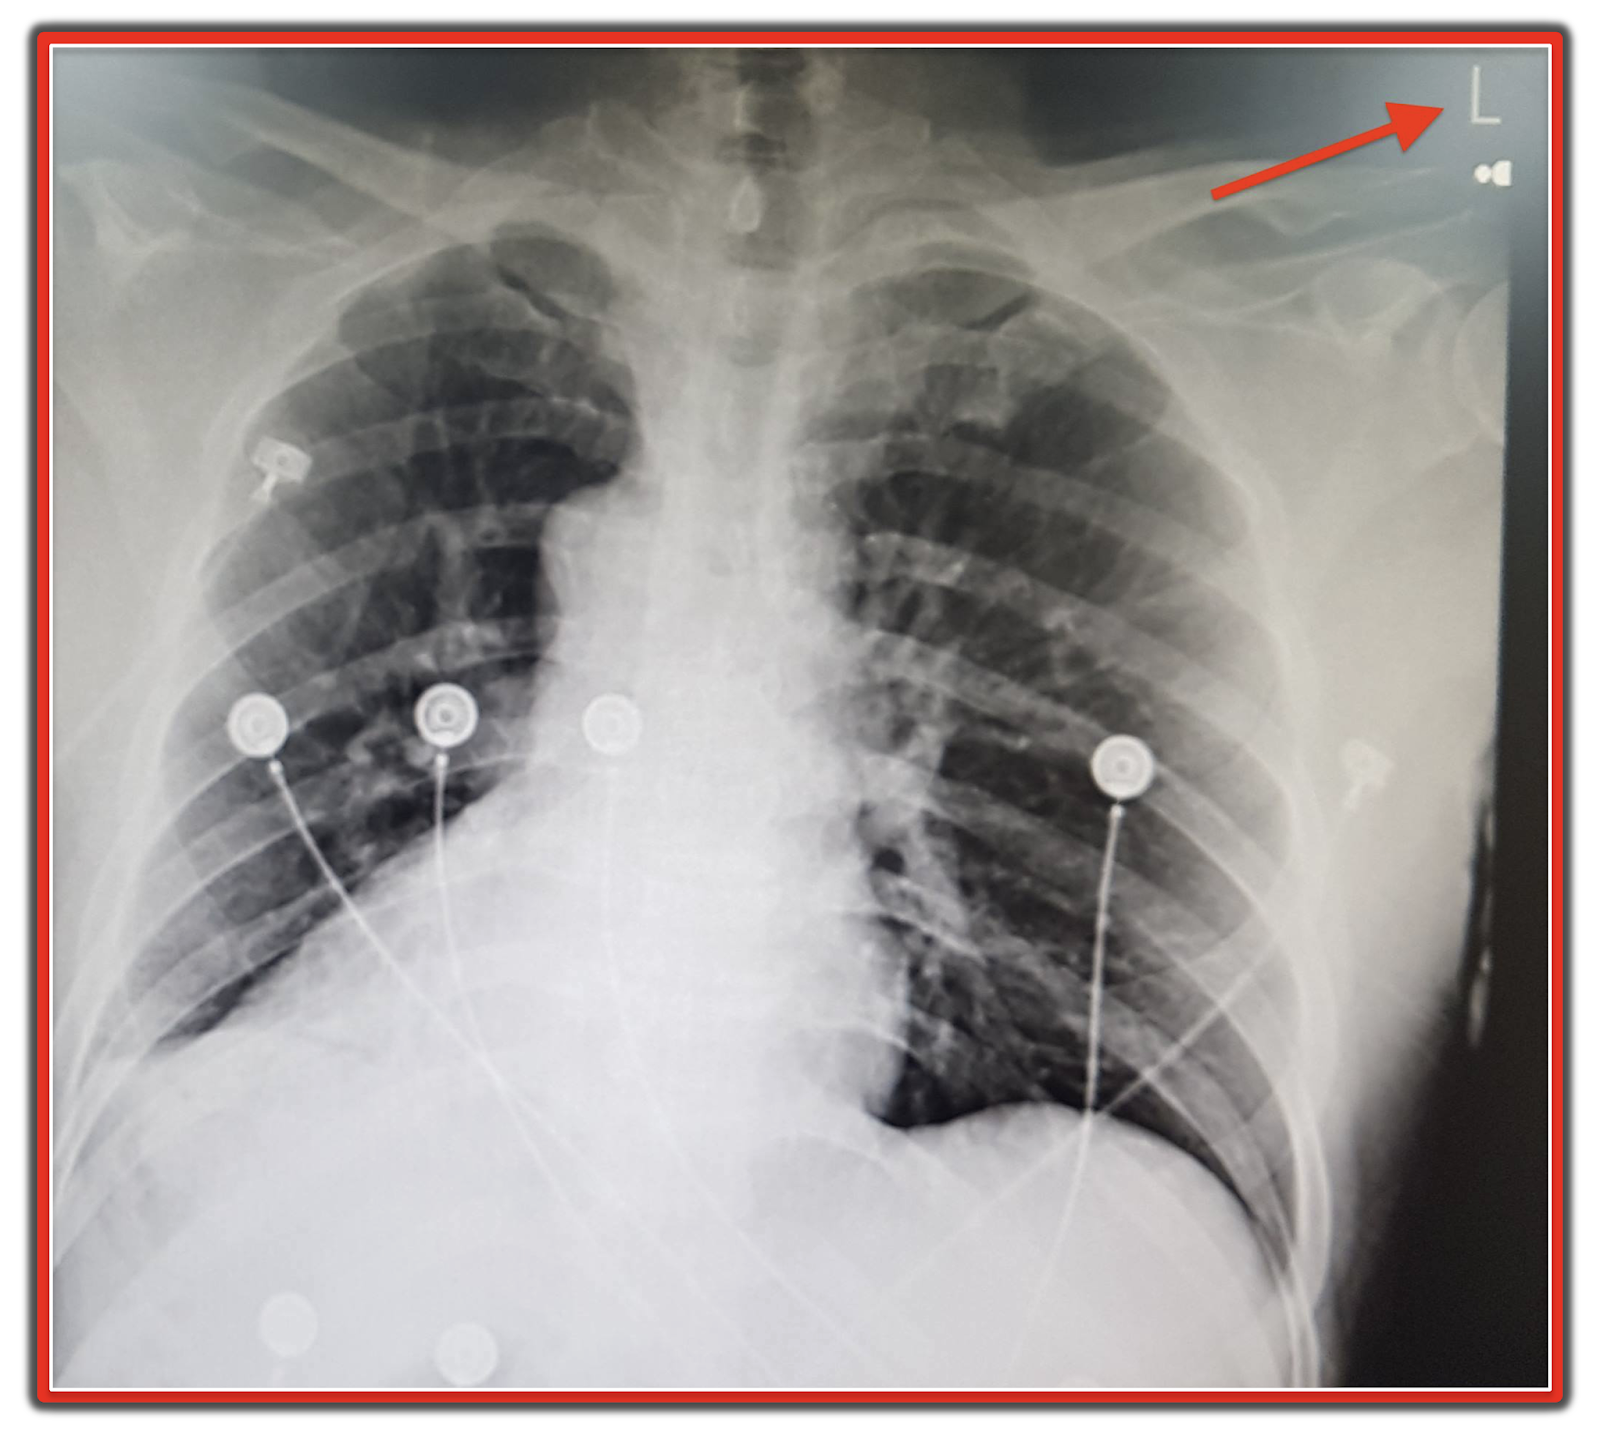

Pacemaker Chest X Ray

Dual chamber pacemaker Chest Xray both atrial and ventricular leads Lead Vs X Ray the measured le generally exceed the specifications. lead components and fixation mechanisms. Lead, in its pure form, is brittle. the tip of the ventricular lead is positioned in the apex of the right ventricle, which is located to the left of the spine on. The difference is most significant at lower tube potentials, and especially. Lead Vs X Ray.